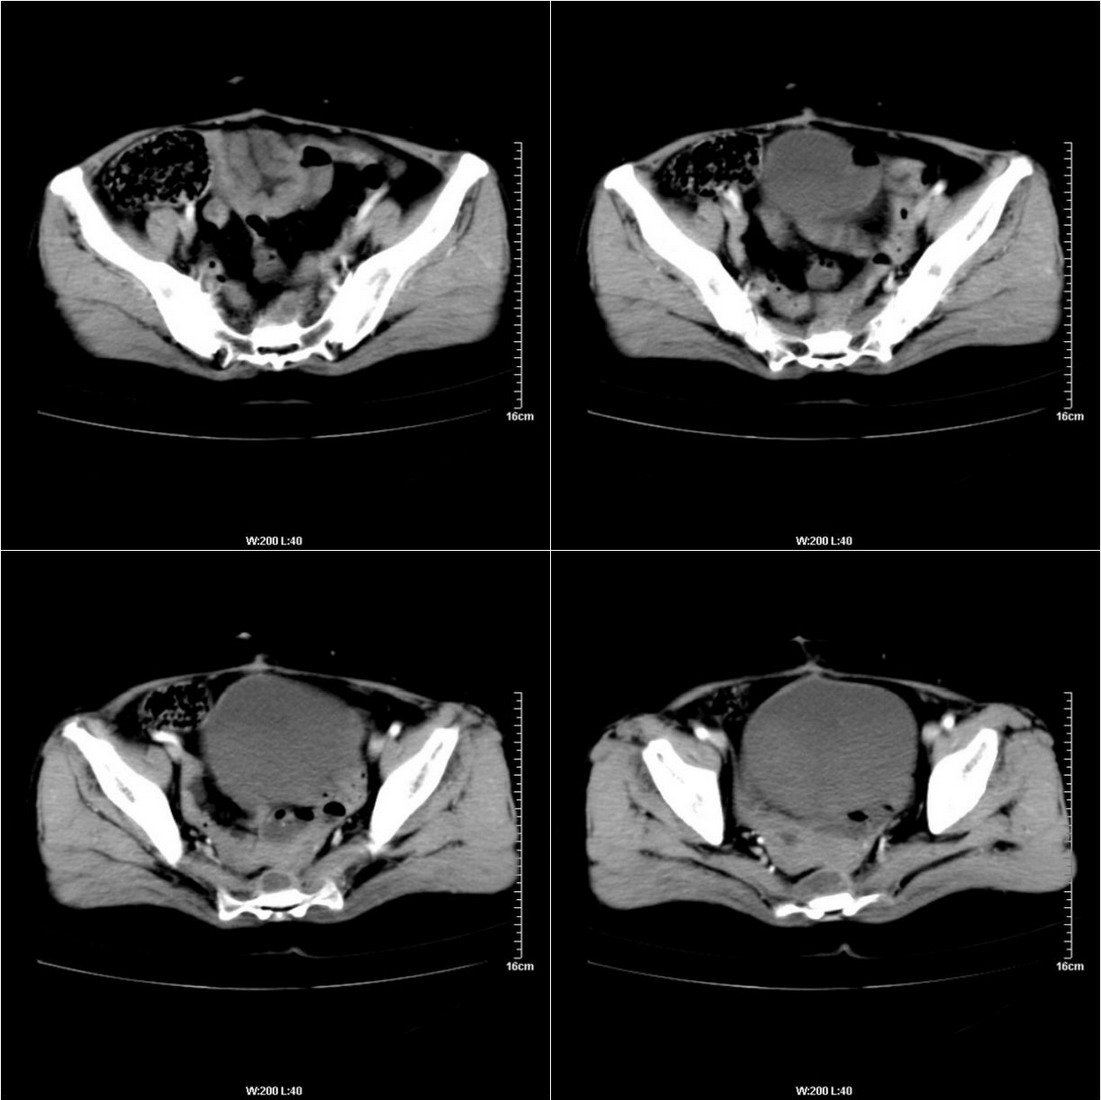

骶骨前侧囊状低密度影,考虑:术后改变.余未见明显异常.

直肠癌术后人工肛门,骶前及术区结节及囊状影,强化不明显,考虑术后瘢痕及粘连包裹可能大,转移不除外。

直肠癌术后骶骨前转移或复发

膀胱壁见索条状软组织密度影伴强化,可考虑炎性肉芽肿样增生改变,常见于放疗后或慢性感染;直肠及周围软组织见肿块,轻度强化,考虑直肠癌术后复发,并侵犯周围组织